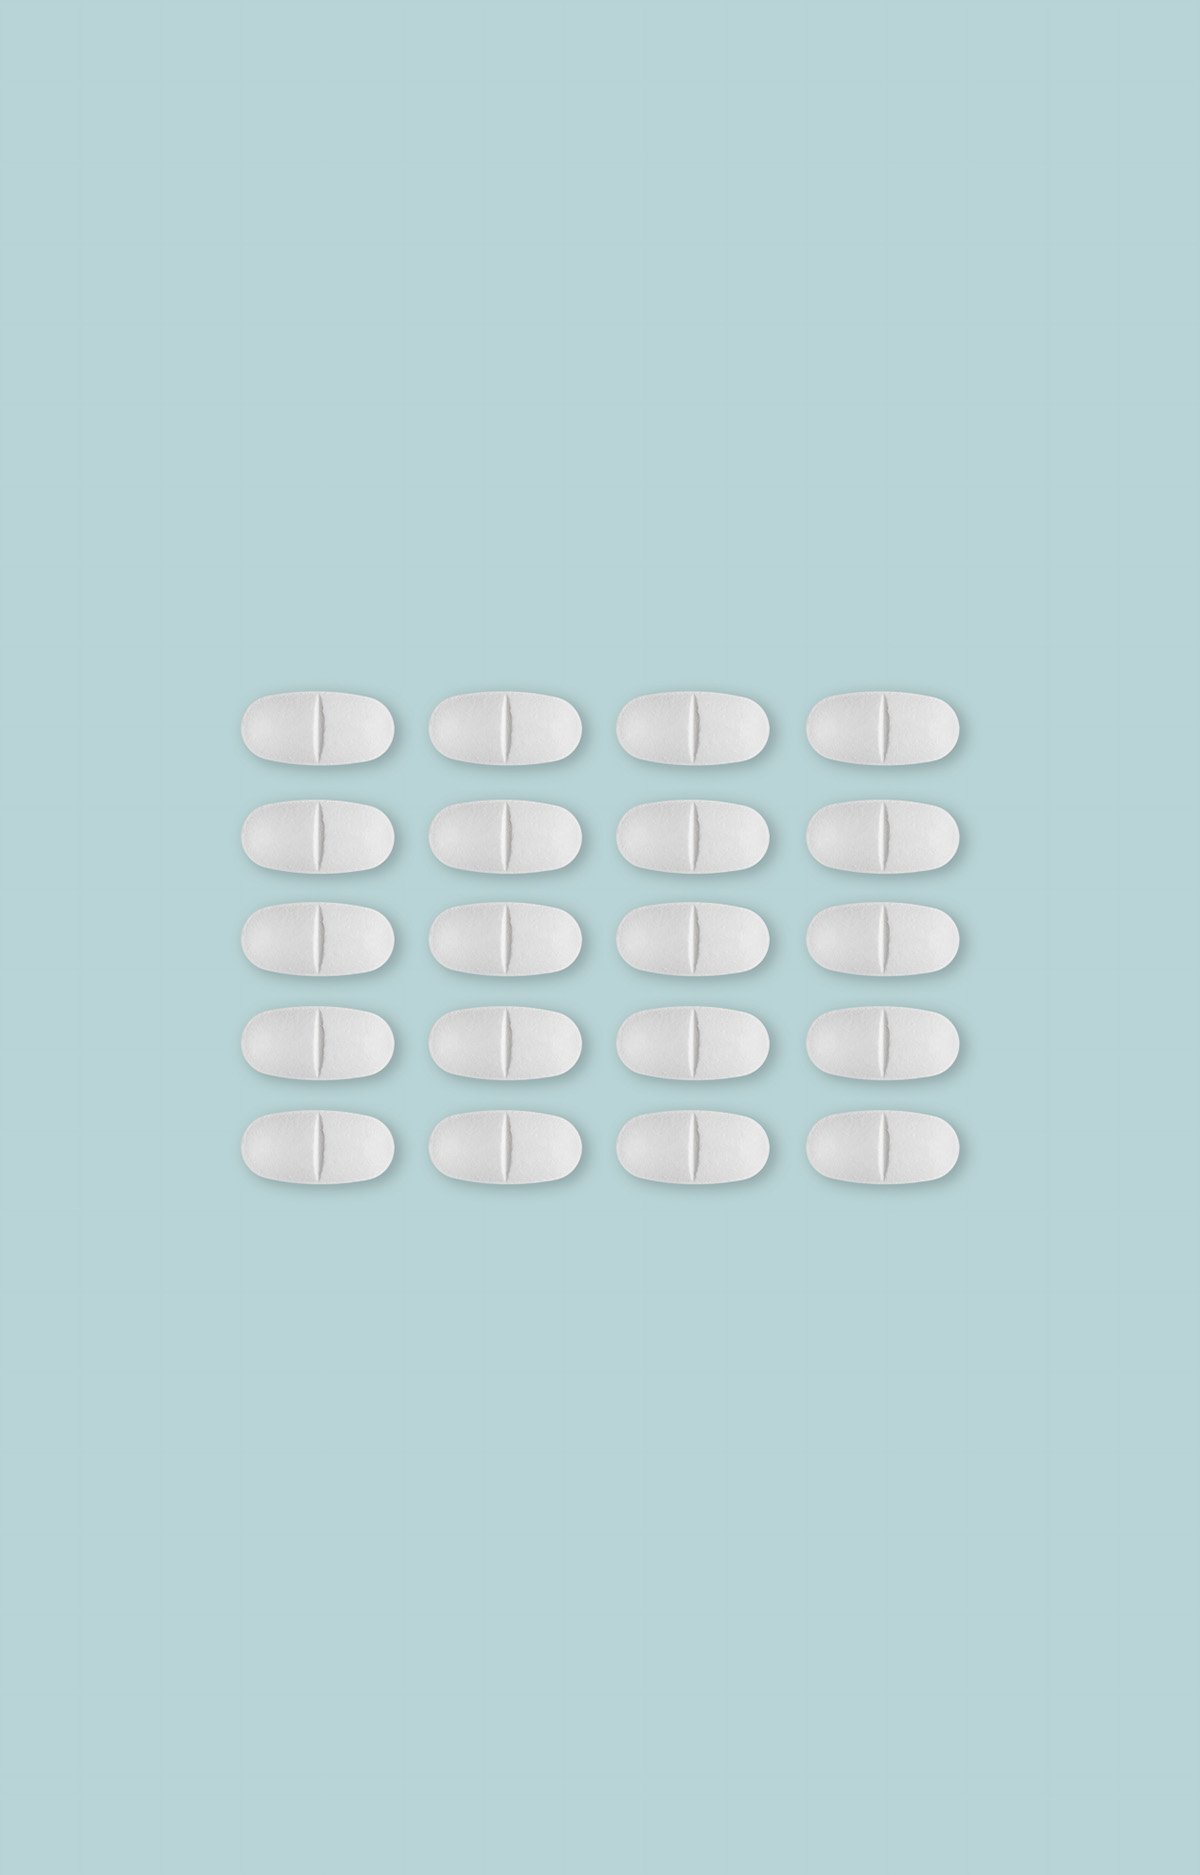

¿Pero esas fotos por sí solas cuentan algo?, se debate en la mesa mientras en el escenario la fotógrafa Juliette Pavy recoge el premio Photographer of the Year por su magnífico trabajo sobre el programa de contracepción forzada llevado a cabo en Groenlandia hace décadas.

La pregunta es muy pertinente, pero lo cierto es que los delicados retratos y las imágenes que componen la narrativa del reportaje Spiralkampagnen -en referencia a la espiral usada como método anticonceptivo forzoso en mujeres inuit- le han valido a la francesa el máximo galardón de esta edición de los premios, así como el primer premio en la categoría de Proyectos de Documentación.

Imágenes que rehuyen de la inmediatez y la actualidad y se centran en un trabajo de largo recorrido dispuesto a desenterrar historias dolorosas y abordar ese trauma colectivo, concendiendo a las víctimas todo el protagonismo.